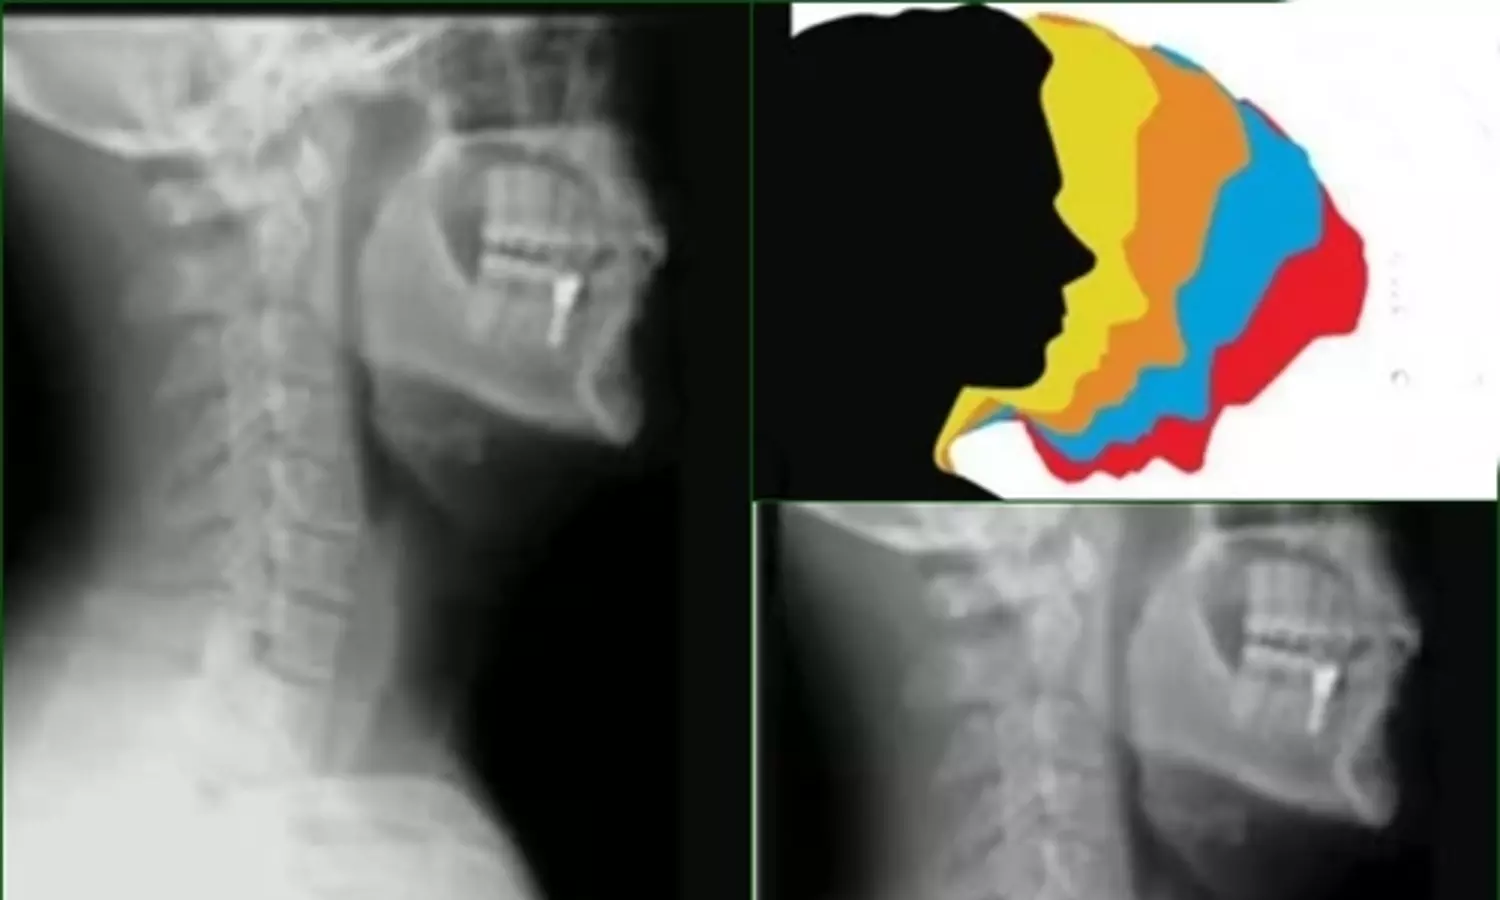

Representative image (Photo: IANS)